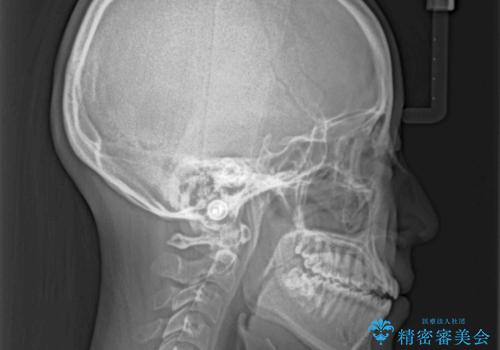

受け口と開咬を急速拡大装置とワイヤー装置で改善

- 前歯の開咬と、受け口による咬み合わせの悪さを気にして来院された患者様です。

上顎歯列が狭窄していたため、急速拡大装置により上顎骨を側方に拡大し、その後ワイヤー装置にて矯正治療を行うこととしました。

舌の突出癖が開咬の原因であったので、改善のための舌トレーニングを行っていただきました。

舌トレーニングは後戻りにも大きく影響するため、とても重要なトレーニングです。